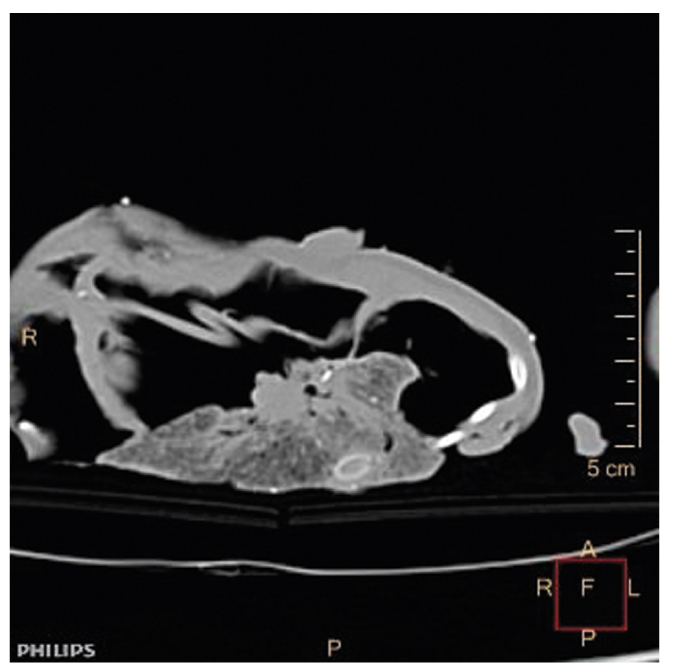

ПРИМЕРЫ ИЗ ПРАКТИКИ

В обоих случаях КТ выполнена на досекционном этапе в день обнаружения трупов на мультиспиральных компьютерных томографах с толщиной среза 1,5 и 2 мм. В обоих случаях трупы были доставлены в герметичных плотных полиэтиленовых мешках. Проведено стандартное нативное (без применения контрастных средств) КТ-исследование тел от свода черепа до пальцев стоп в положении трупов на спине с согнутыми руками и ногами. В случае № 1 исследование выполнено в отделении лучевой диагностики областной больницы на компьютерном томографе Bright Speed 16 (General Electric, США), в случае № 2 — в рентгенологическом отделении районной больницы на компьютерном томографе Optima (General Electric, США). Анализ полученных аксиальных изображений выполнен в различных диагностических окнах: легочном окне (1000–1600 HU), мягкотканном окне (400–500 HU), костном окне (1500–3000 HU), дополнен построением постпроцессинговых мультипланарных и объемных реконструкций.

Рис. 6. КТ, сагиттальная реконструкция, костное окно: ядра окостенения в грудине.

Fig. 6. Computed tomography, sagittal reconstruction, bone window: kernel of ossification in the sternum.

Зрелость плодов рентгенологически устанавливалась по наличию ядер окостенения в грудине, сформированности хрящей носа и ушных раковин.